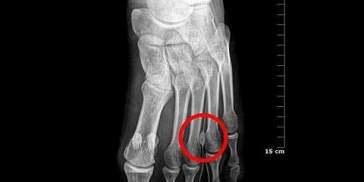

L'origen d'aquesta degeneració és atribuïda a la compressió del nervi en l'espai entre 3r i 4t cap metatarsià. Aquesta és la localització més freqüent perquè es produeix la unió entre les branques dels nervis plantars intern i extern, determinant una fixació més gran del nervi, el que l'exposa més als microtraumatismes. A més, en aquesta zona s'acompanya més sol·licitació mecànica durant les diferents fases de la marxa pels moviments entre les dues columnes, interna i externa, del peu.

El diagnòstic d'aquesta patologia és essencialment clínic, però és útil realitzar una valoració radiològica dels peus en càrrega per descartar patologies que poden donar símptomes similars i per valorar la fórmula metatarsiana de l'avantpeu.